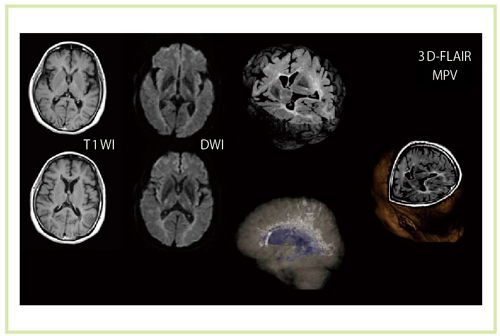

図3 脳腫瘍症例における種々のシーケンスによる画像(Titan 3T)